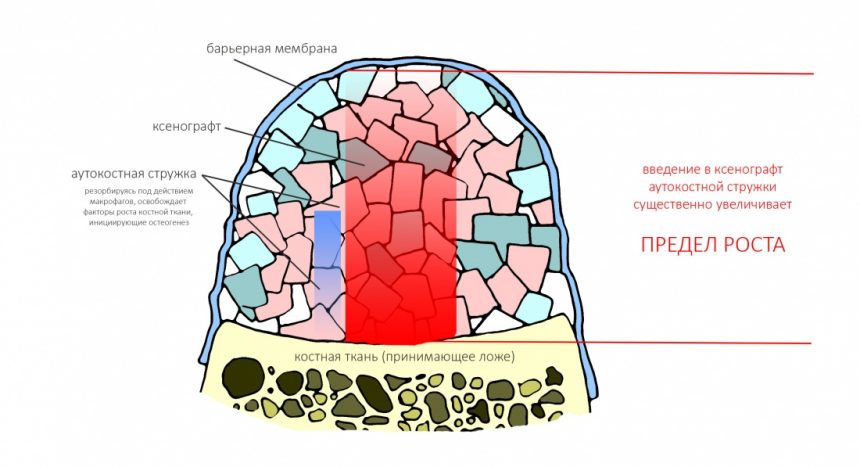

Создание смешанного графта (т. е. введение в биоматериал аутокостной стружки) серьезно расширяет предел роста, но не преодолевает его. Причём, лишь небольшая (около 30%) аутокостной стружки участвует в регенерации, остальное «съедается» остеокластами и прочими макрофагами, при этом освобождаются т. н. «факторы роста» костной ткани — гормоноподобные вещества, инициирующие механизм остеогенеза: